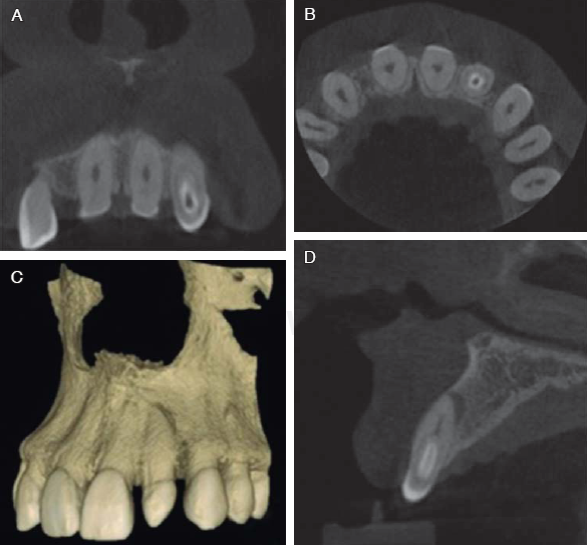

Figura 3 Cortes tomográfi cos: A) corte frontal, B) corte coronal, C) reconstrucción cone-beam, D) corte sagital; se muestra diferentes vistas del dens in dente.

Con la finalidad de obtener un diagnóstico más preciso, se realizó una TAC cone-beam, donde pudimos confi rmar una invaginación del esmalte hasta tercio medio de la raíz. Con base en la clasificación de Oehlers, nuestro diagnóstico correspondió a un dens in dente tipo II (Figura 3). Se realizaron pruebas de sensibilidad pulpar con frío y calor, las cuales fueron negativas. Las pruebas periodontales también fueron negativas, por lo que se diagnosticó como necrosis pulpar con periodontitis apical asintomática.

Ballal, en 2007, sugiere la utilización de auxiliares diagnósticos como la tomografía y el cone-beam, ya que ofrecen mayor información y detalles de las anomalías dentales; en el presente caso se muestra el uso de cone-beam y gracias a las imágenes proporcionadas fue posible tener información fiable para implementar plan de tratamiento; además, autores como Gangwar (2014) mencionan que el tratamiento dependerá de las características presentes, así como de acuerdo a la clasificación propuesta por Ohelers, esto debido a que se preferirá realizar tratamientos conservadores y en muy pocos casos cirugía apical o inclusive la extracción.10,11,13,14

El actual caso se diagnosticó como un tipo II según la clasificación de Oehlers debido a la extensión de la invaginación hasta tercio medio de la raíz. Debido a esta invaginación y la comunicación con el medio bucal, el diente se diagnosticó con necrosis pulpar y periodontitis apical asintomática. De Oliviera en 2008 menciona que la irrigación en dientes necróticos debería ser activa con puntas endodóncicas y el ultrasonido, para poder garantizar la desinfección del sistema de conductos radiculares, como se realizó en el presente caso clínico; además, De Smith, en 1982, recomienda numerosas técnicas de obturación para los dens in dente, las más utilizadas son la compactación vertical y la gutapercha termoplastificada.22-24

El uso de auxiliares de diagnóstico tales como la tomografía o imágenes 3D siempre nos proporcionarán un diagnóstico certero para ofrecer el tratamiento menos invasivo y que el pronóstico sea el más favorable, así como el uso de ultrasonido y técnicas de obturación de gutapercha modificada, con la finalidad de dar un mejor pronóstico a los pacientes.